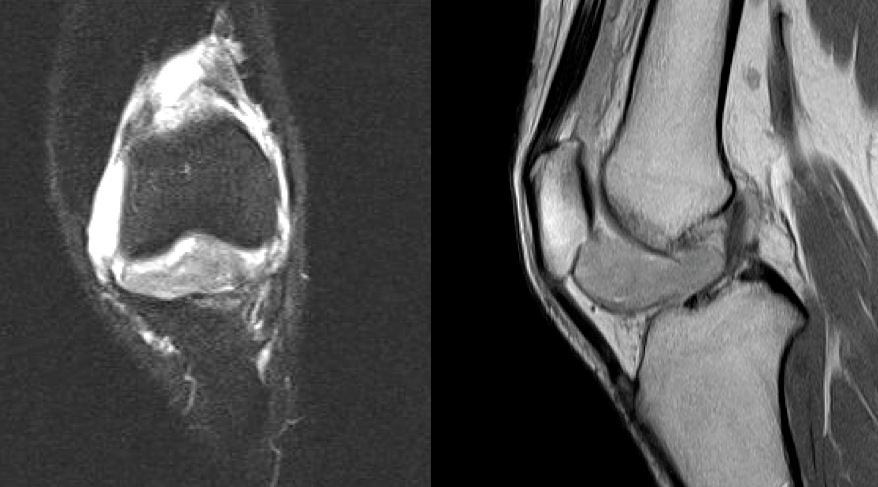

Figure 4 for case pigmented villonodular synovitis ( RID3641 )

Figure 4